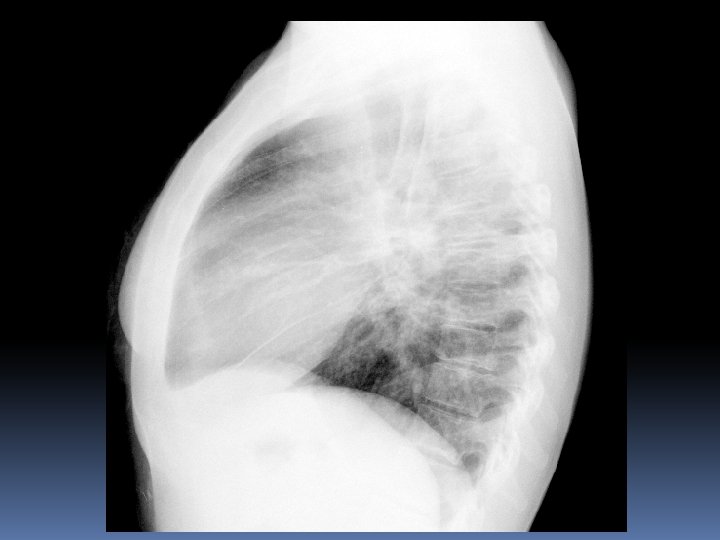

X 2007 Mujer 26 años Astenia, adelgazamiento 5 kg en 3 -4 meses. Nerviosa. Problemas de pareja. Hace 15 dias : tos seca y dolor en costado izquierdo por lo que acude a Urgencias del hospital. No fiebre termometrada. Dolor en costado Izquierdo de características pleuríticas. Auscultación normal. Sat 98%.

Un mes mas tarde……. .